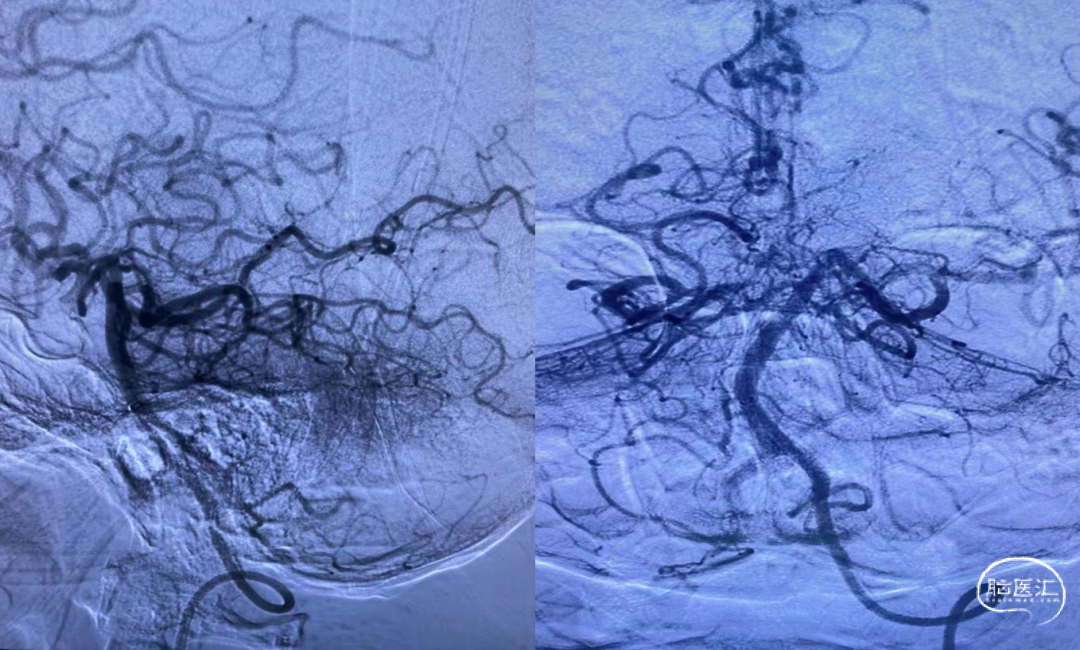

脑血管造影提示:左侧颈内动脉起始段重度狭窄,基底动脉尖闭塞,栓塞可能性大

Neuron max 6F 长鞘快速至左侧椎动脉V2段。

微导丝引导ACE 68抽吸导管,将抽吸导管ACE 68送至基底动脉闭塞近端,接触血栓后并深入血栓2MM左右。

持续保持负压约2分钟后,持续负压抽吸下缓慢撤出抽吸导管,撤出抽吸导管过程中出现回血通畅。手推造影,见基底动脉显影良好,双侧大脑后动脉显影良好,双侧小脑上动脉显影良好,TICI 分级3级。